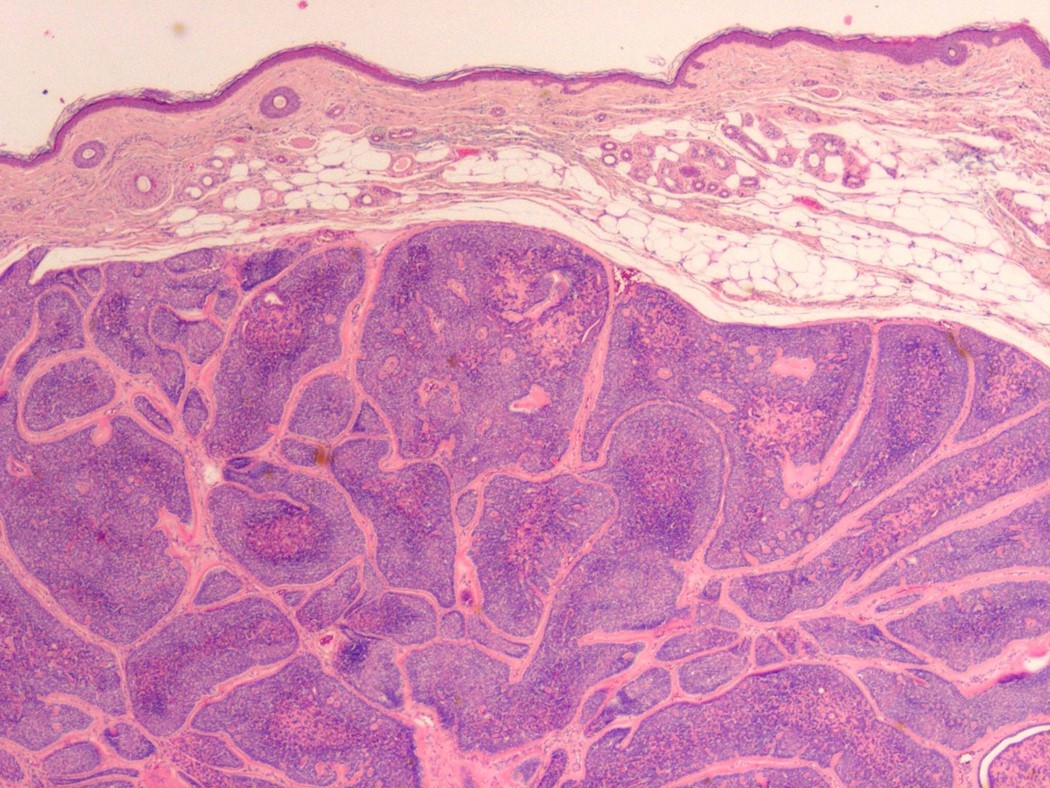

What disease process is pictured below?

Acanthosis Nigricans

Fibroepithelial polyp